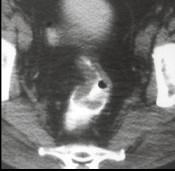

男,53岁,便秘、血便,大便变细,CT如图,应考虑为()A.肠Crohn病B.直肠结核C.溃疡型直肠癌D.慢性溃疡性结肠炎E.直肠淋巴瘤

问题 男,53岁,便秘、血便,大便变细,CT如图,应考虑为()

选项 A.肠Crohn病 B.直肠结核 C.溃疡型直肠癌 D.慢性溃疡性结肠炎 E.直肠淋巴瘤

答案 C